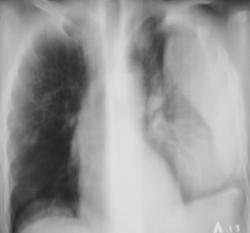

Пациент мужчина преклонного возраста в «критическом состоянии» доставлен машиной скорой помощи «прямо в рентгеновский кабинет». Температура, разлитые сильные боли слева в грудной клетке, интоксикация. Сделана рентгенограмма только в прямой стандартной проекции (иллюстрация 1). Решено назначить противовоспалительную и дезинтоксинационную терапию и после улучшения состояния провести рентгенологическое исследование. Через 1 неделю пациенту субъективно «стало лучше» доставлен в рентгеновский кабинет.